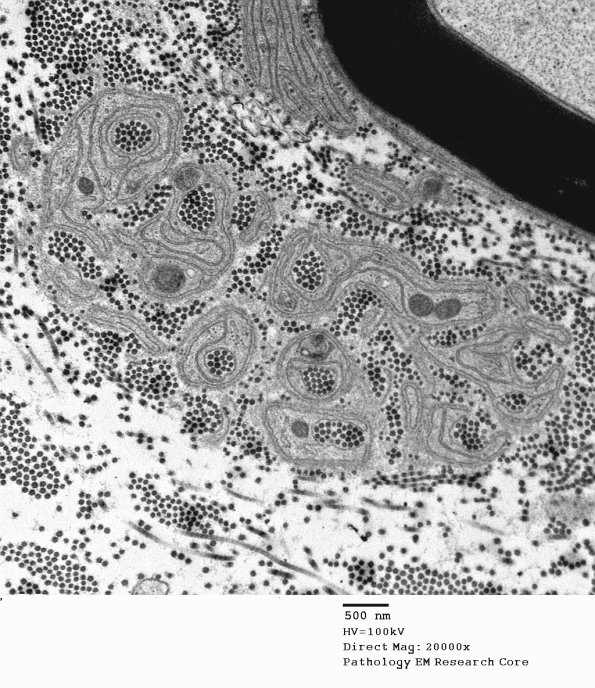

Additional examples of collagen pockets signifying substantial numbers of lost unmyelinated axons.